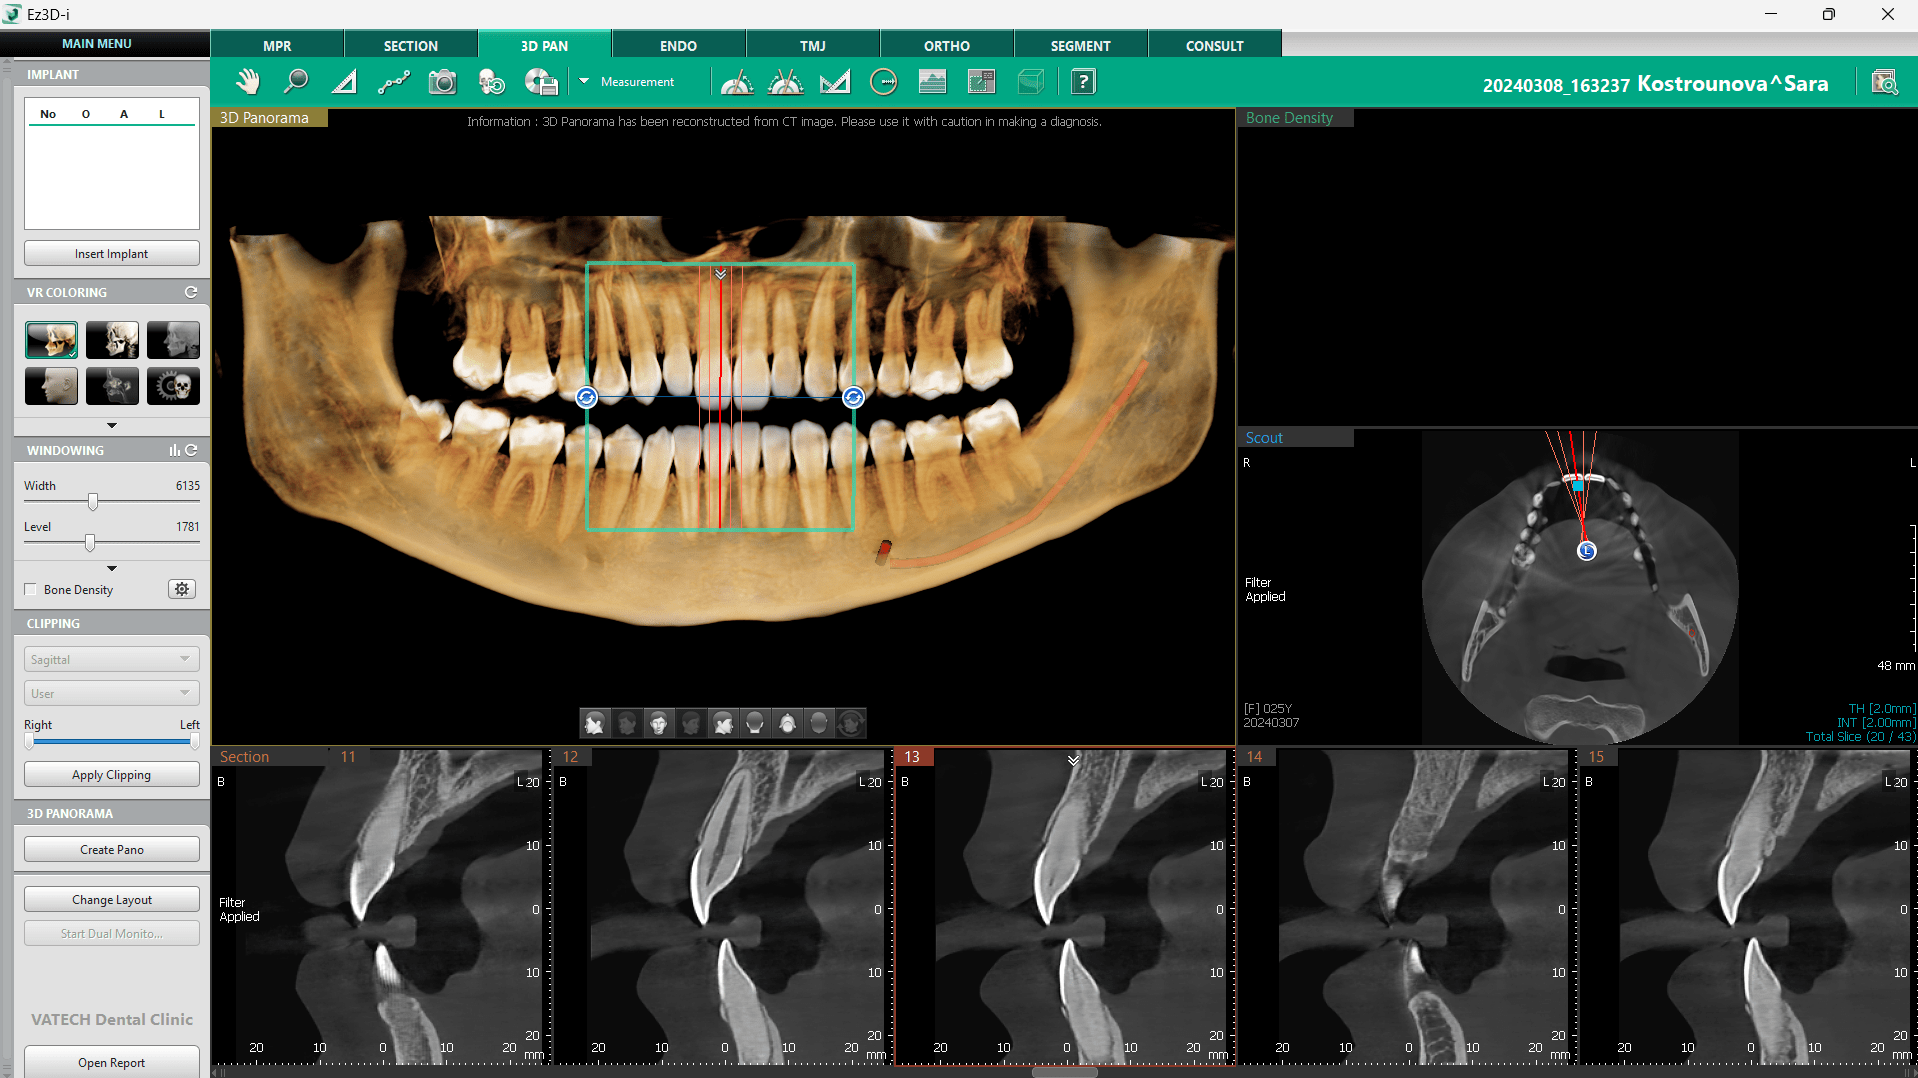

3D Navigator este un instrument esențial al tab-ului 3D PAN din software–ul de planificare a implanturilor dentare Ez3D-i. Funcția ajută la navigarea prin diferitele secțiuni ale scanării CBCT afișate în partea inferioară a ecranului. Acest lucru este esențial pentru a vizualiza detaliile anatomice ale zonei în care se va plasa implantul.

Vizual reprezentat sub forma unui pătrat verde, cu linii verticale și orizontale plasate în centru, prin intermediul 3D Navigator, se poate seta intervalul dintre secțiunile afișate făcând click dreapta pe imaginile secțiunilor și selectând opțiunea „Interval”. Liniile roșii din Navigator indică numărul și distanța dintre secțiuni.

Funcția de rotație a 3D Navigator permite o vizualizare completă a secțiunilor imagistice, oferind un control intuitiv asupra vizualizării. Utilizarea acesteia este facilă și intuitivă datorită unor comenzi rapide de la tastatură, iar revenirea la poziția inițială se poate realiza rapid printr-un dublu click.

2. Vizualizarea panoramică 3D

Vizualizarea panoramică 3D este una dintre cele mai utile funcții din software-ul imagistic, transformând scanările CT într-o imagine panoramică detaliată. Această funcție oferă o perspectivă de ansamblu asupra structurii osoase și ajută la identificarea eventualelor anomalii, facilitând diagnosticul. Acest lucru o transformă într-un instrument de analiză extrem de eficient, dacă medicul ține cont de limitările sale rezultate din procesul de reconstrucție. Totuși, chiar dacă alături de 3D Navigator este un instrument puternic, ea nu este concepută pentru a fi singura sursă de diagnostic.

Accesarea acestei funcții se poate face prin selectarea opțiunii „Change Layout” din colțul stâng jos al ecranului, alegând dintre mai multe configurații care includ vizualizarea 3D PAN. De asemenea, există posibilitatea de a afișa fereastra „Implant Bone Density”, extrem de utilă în implantologie.

Vizualizarea 3D PAN poate fi personalizată prin ajustarea curburii imaginii. Aceasta se poate realiza selectând un layout cu fereastră 3D PAN și accesând opțiunea „Create Pano” în colțul din stânga jos al ecranului. Va apărea o fereastră de dialog, care permite personalizarea vizualizării 3D PAN și optimizarea imaginii finale pentru o analiză detaliată.

3. Trasarea canalului mandibular

Localizarea canalului mandibular este esențială pentru stabilirea unei abordări corecte în planificarea implanturilor. Software-ul Ez3D-i oferă mai multe metode pentru marcarea acestuia în imaginile 3D, iar utilizarea 3D PAN reprezintă una dintre cele mai rapide și eficiente modalități. Combinarea 3D Navigator cu imaginea panoramică 3D, generată dintr-o scanare CT, oferă o modalitate rapidă de a naviga prin secțiuni și de a localiza canalul.

Procesul începe prin selectarea opțiunii „Draw Canal” din bara de instrumente din partea de sus a ecranului și inițierea trasării de la foramen mentale, punctul optim pentru începutul delimitării canalului mandibular. 3D Navigator joacă un rol important în acest proces, facilitând identificarea precisă a canalului. Odată găsit, canalul poate fi marcat cu ajutorul butonului stâng al mouse-ului, iar navigarea prin secțiuni se poate face utilizând rotița de scroll. În cazul unei erori, punctele trase anterior pot fi șterse rapid cu printr-un click pe butonul drept al mouse-ului.

După completarea trasării, linia canalului se finalizează printr-un dublu click, iar dacă este necesară o ajustare, traseul poate fi editat sau șters în orice moment printr-un click dreapta pe linie. Această funcție oferă medicilor siguranța că implanturile pot fi plasate în poziția optimă, minimizând riscurile de afectare a structurilor nervoase.